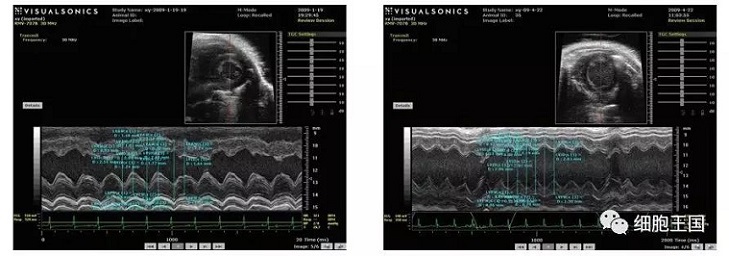

干細胞移植后各臟器呈現(xiàn)較之前狀態(tài),具體表現(xiàn)在以下幾個方面(如圖)。

超聲心動圖顯示對照組左室舒張期容積低于移植組